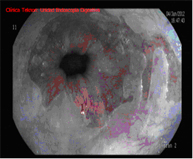

El diagnóstico se lleva a cabo mediante endoscopios de alta resolución con magnificación (aumento de la imagen), utilizando técnicas de cromoendoscopia añadidas, realizadas por endoscopistas especialistas en el diagnóstico precoz de lesiones precancerosas y la realización de biopsias que son analizadas.

Barrett 1Barrett 1 Barrett 2Barrett 2